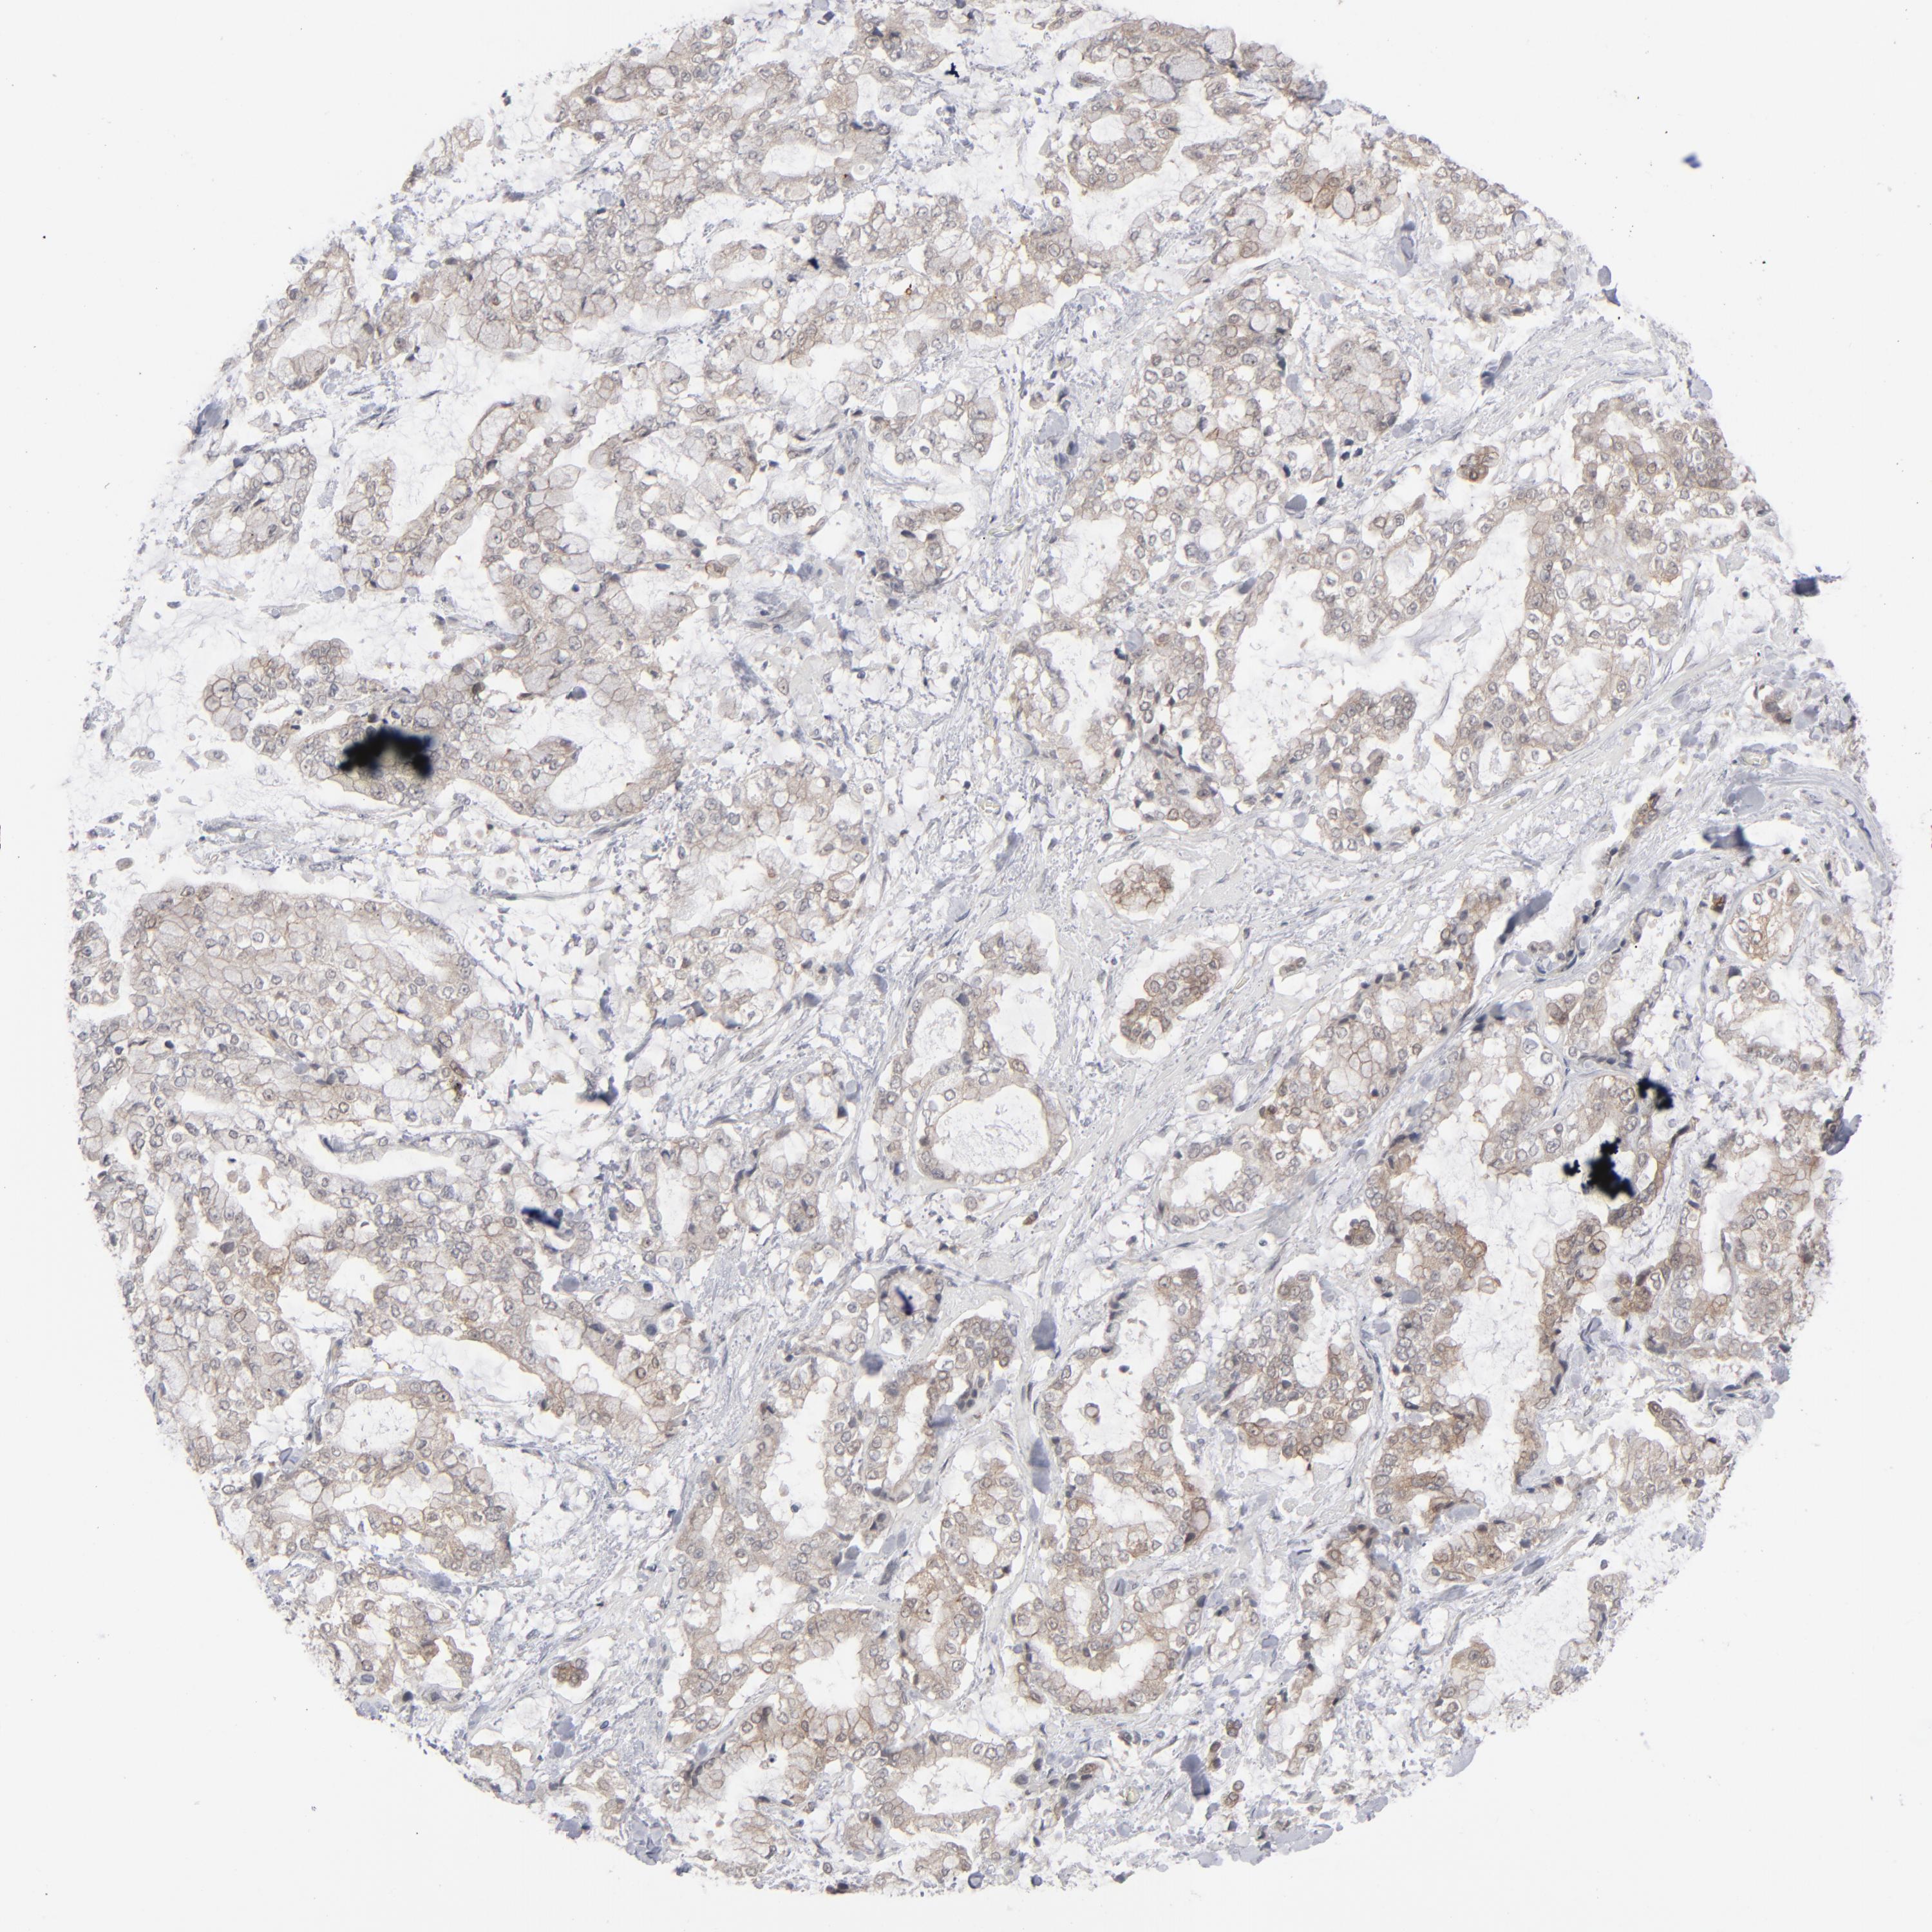

STOMACH CANCER - Protein expressioni

A mouse-over function shows sample information and annotation data. Click on an image to view it in a full screen mode. Samples can be filtered based on level of antibody staining by selecting one or several of the following categories: high, medium, low and not detected. The assay and annotation is described here.

Note that samples used for immunohistochemistry by the Human Protein Atlas do not correspond to samples in the TCGA dataset.

Antibody stainingi

Antibody staining in the annotated cell types in the current human tissue is reported as not detected, low, medium, or high, based on conventional immunohistochemistry profiling in selected tissues. This score is based on the combination of the staining intensity and fraction of stained cells.

Each image is clickable and will lead to virtual microscopy that enables deeper exploration of all samples and also displays staining intensity scores, fraction scores and subcellular localization as well as patient and tissue information for each sample.

Antibody HPA002033

Staining

High

Medium

Low

Not detected

Intensity

Strong

Moderate

Weak

Negative

Quantity

>75%

75%-25%

<25%

None

Location

Nuclear

Cytoplasmic/membranous

Cytoplasmic/membranous,nuclear

Adenocarcinoma, NOS

Adenocarcinoma, High grade